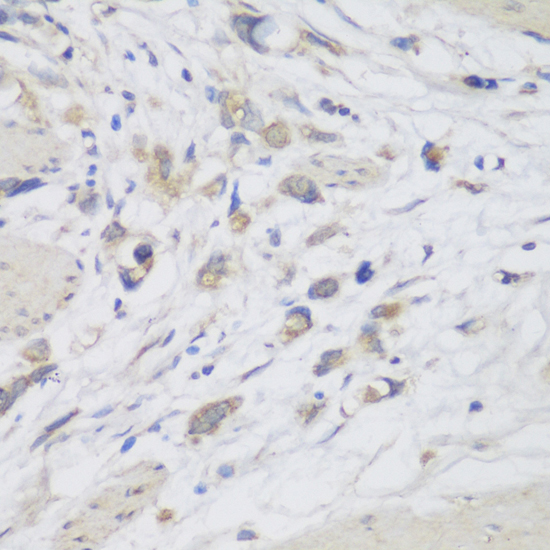

Immunohistochemistry - CEMIP Polyclonal Antibody

Immunohistochemistry of paraffin-embedded human lung cancer using CEMIP antibody at dilution of 1:150 (40x lens).